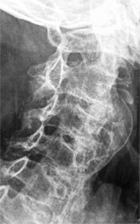

Mr G., 68 ans, présente une dysphagie légèrement calmée par la flexion du rachis cervical. Les bilans digestif et ORL sont normaux. Nos confrères demandent une radiographie du rachis cervical et nous demandent notre avis.

Il est indéniable qu’il existe une très importante hyperostose vertébrale.

L’hyperostose vertébrale ou